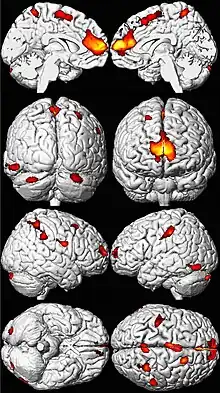

.png.webp)

Lead poisoning can cause a variety of symptoms and signs which vary depending on the individual and the duration of lead exposure.[27][28] Symptoms are nonspecific and may be subtle, and someone with elevated lead levels may have no symptoms.[29] Symptoms usually develop over weeks to months as lead builds up in the body during a chronic exposure, but acute symptoms from brief, intense exposures also occur.[30] Symptoms from exposure to organic lead, which is probably more toxic than inorganic lead due to its lipid solubility, occur rapidly.[31] Poisoning by organic lead compounds has symptoms predominantly in the central nervous system, such as insomnia, delirium, cognitive deficits, tremor, hallucinations, and convulsions.[26]

Lead exposure in children is also correlated with neuropsychiatric disorders such as attention deficit hyperactivity disorder and anti-social behaviour.[76] Elevated lead levels in children are correlated with higher scores on aggression and delinquency measures.[5] A correlation has also been found between prenatal and early childhood lead exposure and violent crime in adulthood.[72] Countries with the highest air lead levels have also been found to have the highest murder rates, after adjusting for confounding factors.[5] A May 2000 study by economic consultant Rick Nevin theorizes that lead exposure explains 65% to 90% of the variation in violent crime rates in the US.[83][84] A 2007 paper by the same author claims to show a strong association between preschool blood lead and subsequent crime rate trends over several decades across nine countries.[85][86] Lead exposure in childhood appears to increase school suspensions and juvenile detention among boys.[87] It is believed that the US ban on lead paint in buildings in the late 1970s, as well as the phaseout of leaded gasoline in the 1970s and 1980s, partially helped contribute to the decline of violent crime in the United States since the early 1990s.[86]